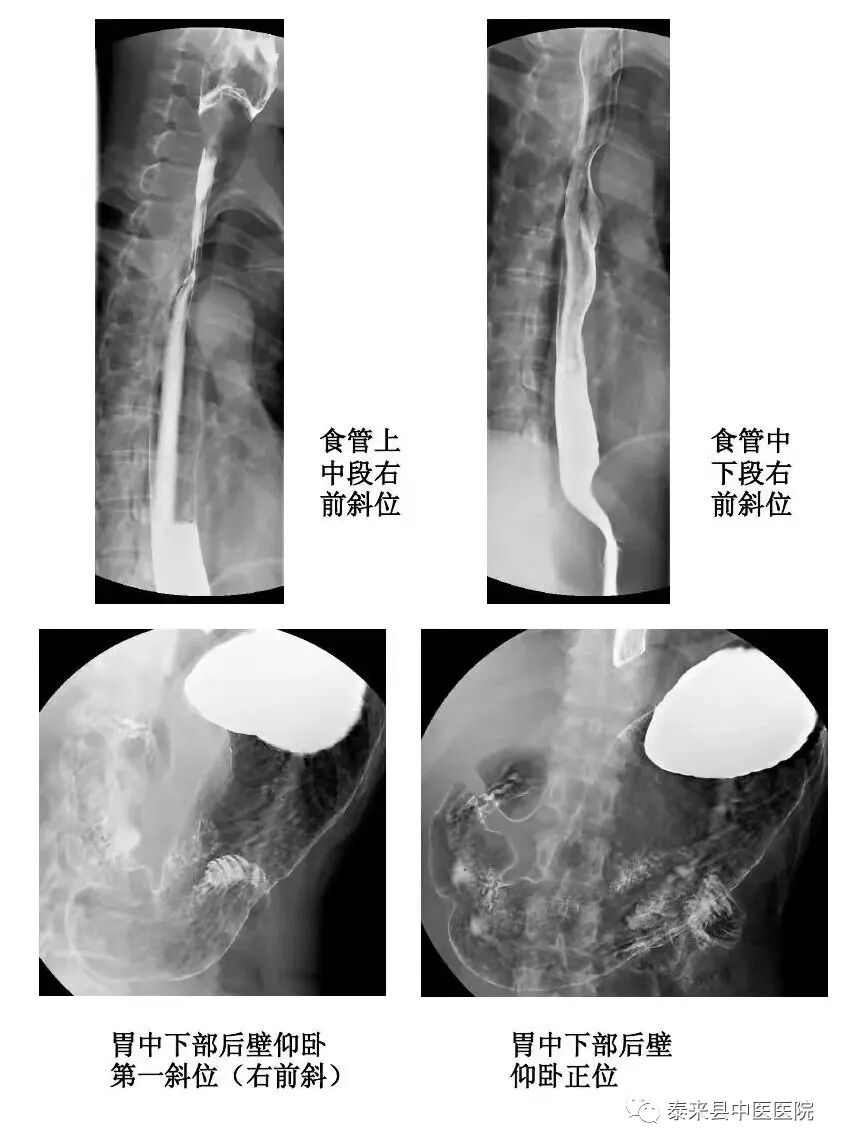

数字化胃肠透视检查以其痛苦微小、快捷安全的优点,对功能性、器质性病变(吞咽功能障碍,贲门失弛缓症,胃下垂,粘膜脱垂等)进行动态实时观察、整体与局部相结合的方法,有效的减少了内镜及CT、MR检查盲区,对术后复查及常规筛查的患者提供了更多的诊断依据。

2、数字化造影

将密度和组织器官有差异的造影剂导入人体检查部位,并检查组织器官是否存在病变。通过动态摄影观察组织器官的功能运行情况,并实时点片摄影。适用于食管、上消化道、全消化道等普通造影及静脉胆道造影、T管造影、静脉肾盂造影、逆行肾盂造影、子宮输卵管造影、膀胱造影、脊髓造影等普通及特殊造影。